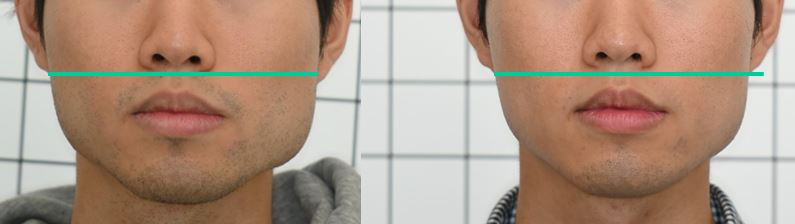

Does this look like ordinary orthodontic treatment to you?

Not long ago, a practicing physician from Prague visited my clinic during orthodontic bracket treatment. She was diagnosed with facial asymmetry and body misalignment, and experienced MCB splint therapy. She was aware that bodily misalignment is related to asymmetry in the facial bones.

Dentistry still remains dominated by the concept of CR (Centric Relation). Many osteopathic physicians have long claimed that the temporal bones move, and treat on that basis, yet the mainstream thinking has not changed. Many dentists still believe that if the mandible (lower jaw) is asymmetric or if the lengths on the right and left differ, surgery is required, and they in fact treat by surgery.